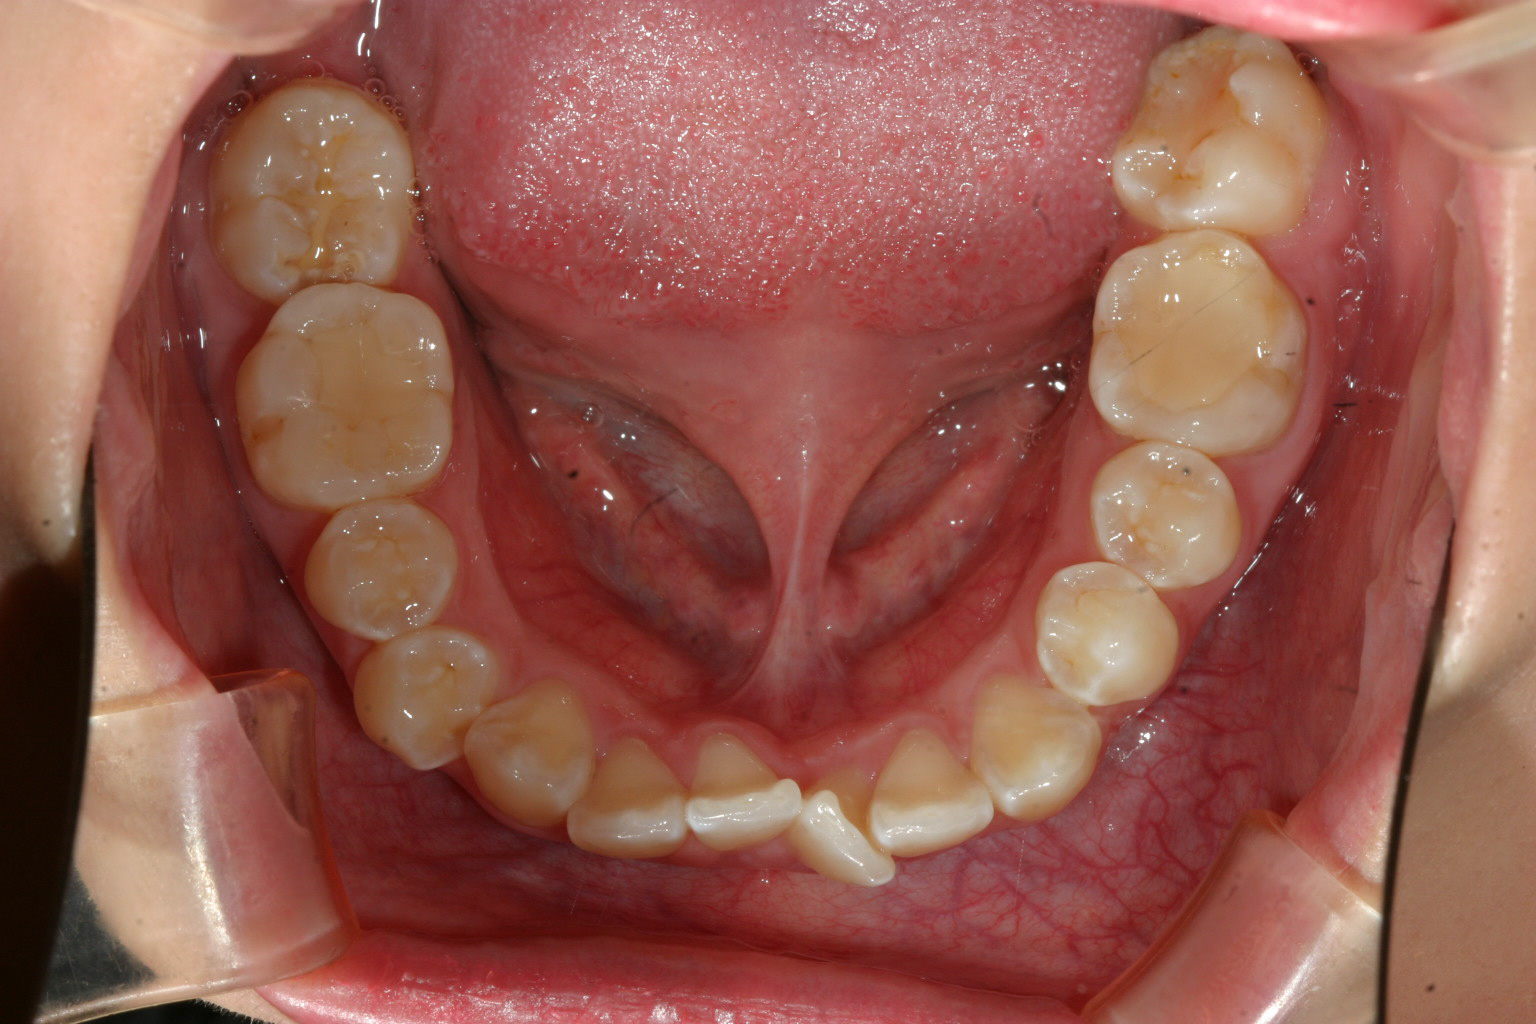

下の前歯もガタガタです。

下顎のガタガタも綺麗になりました。

下顎も結構ガタガタしてましたが患者様の熱心な頑張りで僅か1年4カ月でこの様に綺麗に改善しました。